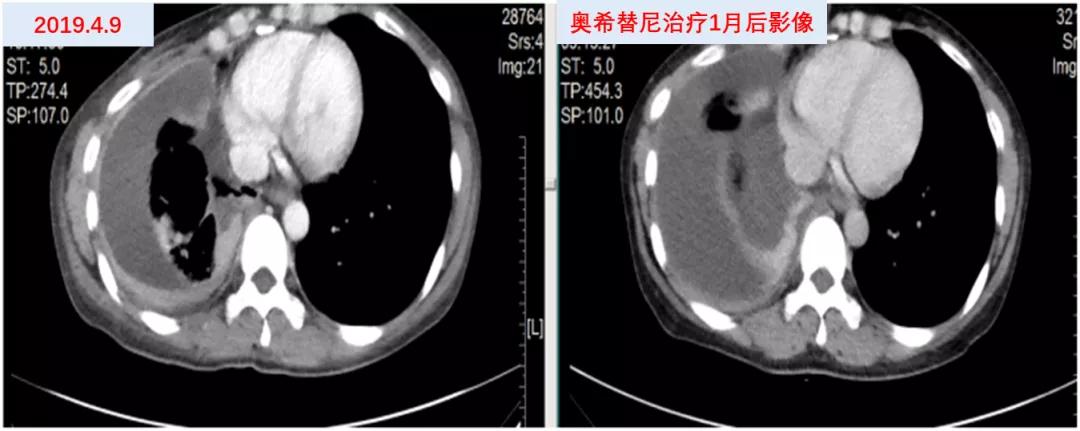

2019年4月2日予右胸腔穿刺置管引流胸水,并予“重组人血管内皮抑制素30mg”(2次)胸腔灌注治疗提高胸水控制率。2019年4月17日分子病理(胸水,ARMS-PCR):EGFR(B19-00081)检测到EGFR基因19del和T790M突变。2019年4月18日开始口服“奥希替尼80mg qd”靶向治疗。2019年5月16日因“胸闷、气促”复查胸部CT示:右侧胸膜增厚,右侧胸腔积液较前增多。疗效评价PD。(图2)

图2 患者奥希替尼治疗前后影像资料